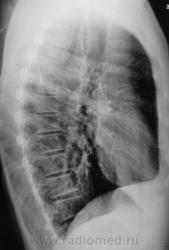

Первое исследование.